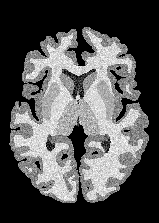

4.2 Registration to a 100 micron ex-vivo brain MRI volume

To showcase the efficacy of our method on real large scale images, we register a 250 in-vivo MRI image (Lüsebrink et al., 2017) to a 100 ex-vivo FLASH human brain volume (Edlow et al., 2019). This represents an inverse problem with more than 11.2B optimizable parameters (compared to 20M for clinical datasets), or 44.8GB of GPU memory. The entire problem does not fit on most GPUs, necessitating distributed multimodal registration. We optimize a composite transform - affine followed by a diffeomorphic mapping; details can be found in Section E.1. Multimodal deformable registration took 58 seconds on 8 NVIDIA A6000 GPUs, which is unprecedented at this resolution. Fig. 6 shows qualitative results, highlighting the ability to register highly detailed structures such as cerebellar white matter; these structures are not visible at macroscopic scales. The resultant advantages of performing registration at this scale can allow researchers to characterize the neuroanatomy at microscopic resolutions and allow morphometric analysis of cortical layers and subcortical nuclei among other structures.